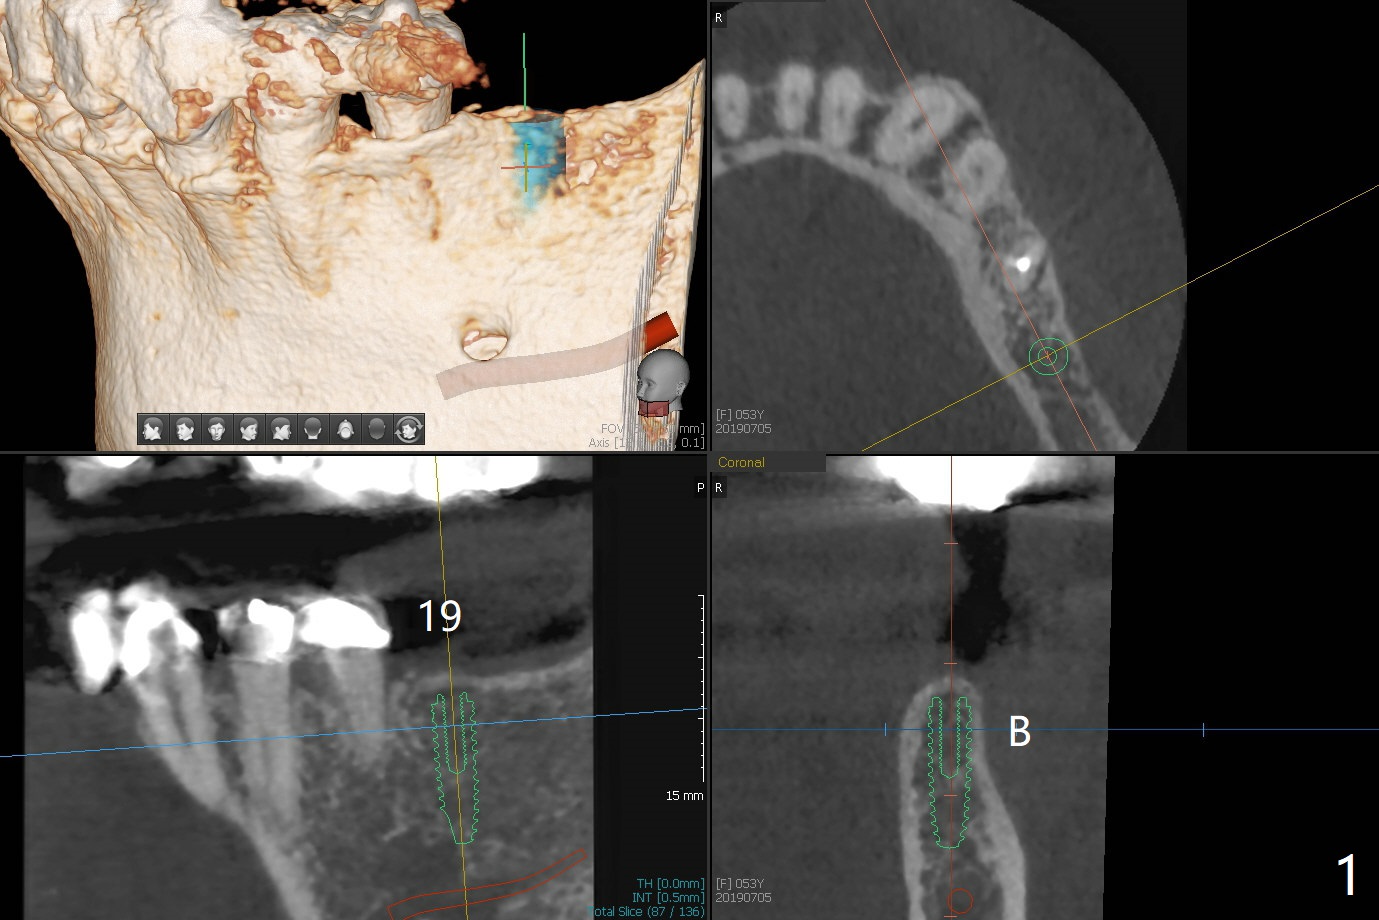

Bone Expansion through Guide

A 53-year-old woman requests implant at #19 after redo #14 crown. The ridge is narrow (holding a 3.5x11.5 mm implant) and apparently low in density (Fig.1). Bone expansion seems necessary. Following use of 2.2 mm drill to the depth, bone expanders will be introduced (1.7/3.1 and 2.4/3.7 mm). After 4.0 mm cortical tap, a 4.0x11.5 mm implant is placed. If torque is high, use 3.5 mm drill. Postop 5x5 cm CT will be taken. Also take pre- and post-op photos of the buccal plate. Prepare surgical handpiece and a new thin fissure bur for ridge split as well as split saw block. Use a UF implant, in consistent with that at #11.